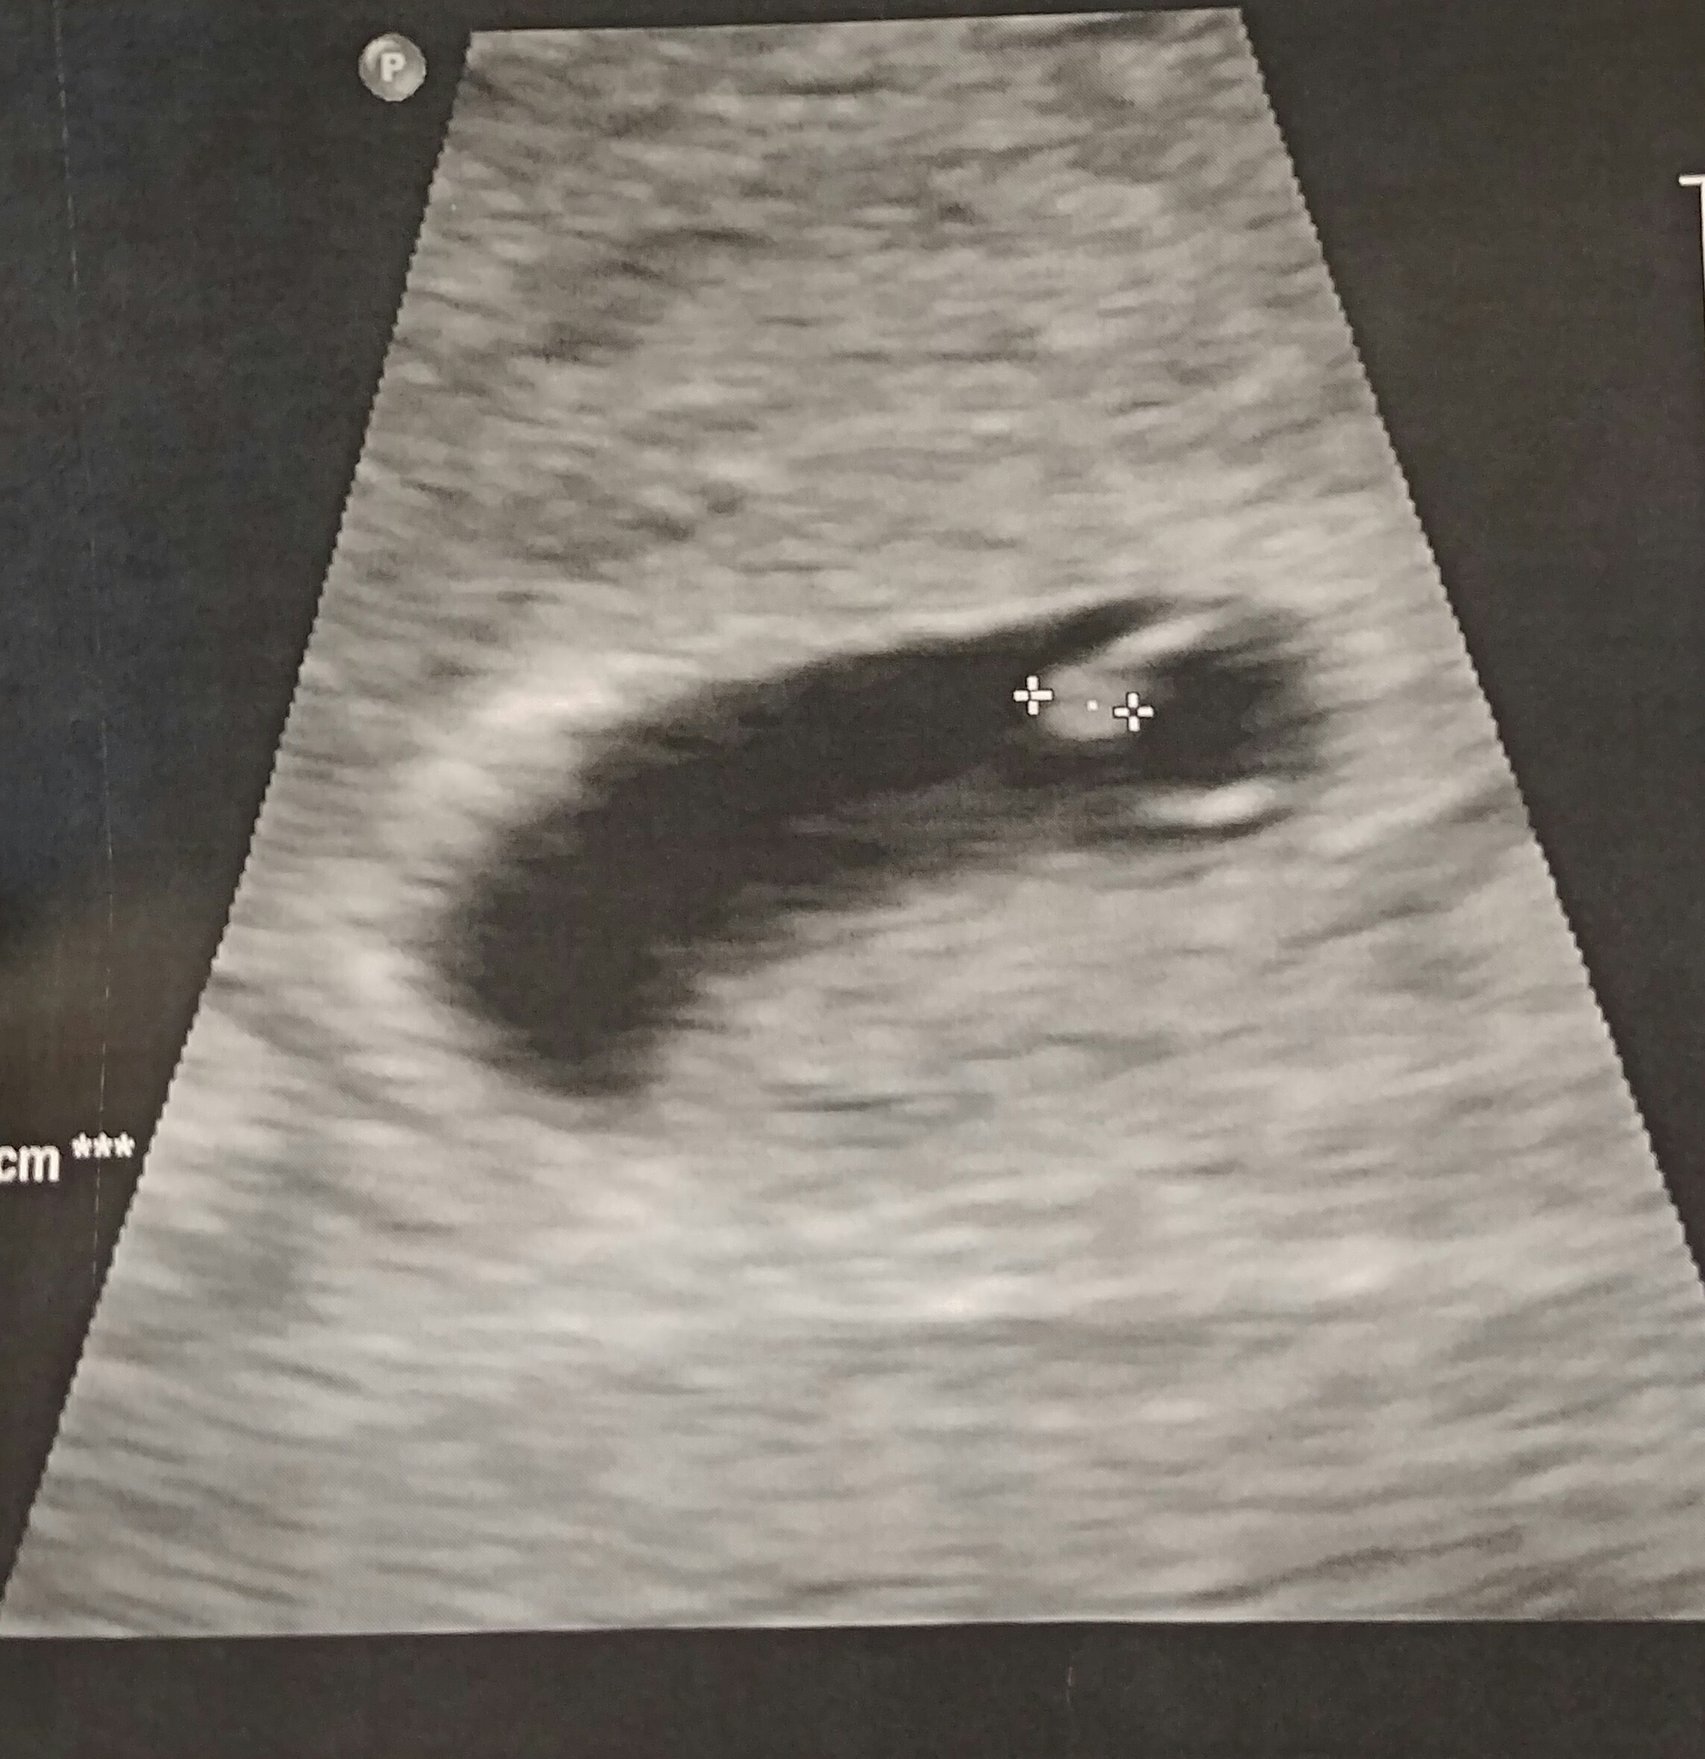

• Ultrasound last Friday measuring at 8w 4d which was a couple days behind what we were thinking but happy to hit the 9w mark today:)